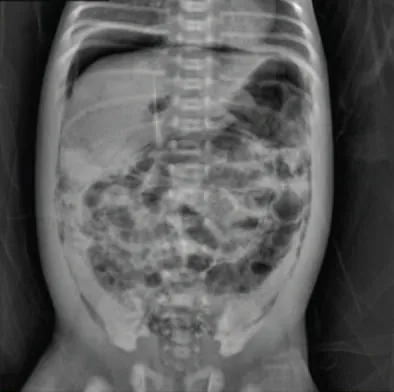

Diagnostics

NEC is clinically diagnosed from the symptoms presented by the infantโ€”abdominal distention, bilious vomiting, and rectal bleeding with bloody stoolโ€”along with an x-ray of the abdomen showing pneumatosis intestinalis, intramural gas in the intestines (Figure 25.17). The only definitive diagnosis is made with a surgical sample or a postmortem assessment with tissue that shows histologic findings of intestinal inflammation, infarction, and necrosis.

An x-ray image of an infant shows gas patterns within the intestinal wall characterized by dark, circular areas against the denser background of the abdomen. The patterns are irregularly distributed throughout the intestine.

Figure 25.17 x-ray of an Infant with NEC This photo shows an abdominal film with pneumatosis intestinalis, a radiologic sign seen in patients with necrotizing enterocolitis (NEC). The abdominal x-ray shows the intramural air bubbles that occur in the bowel wall from gas produced by bacteria in the intestinal wall lining. Note the bubbly lucencies filling the abdominal cavity. (credit: โ€œPneumoperitoneum and Pneumatosis Intestinalisโ€ by Sheng Q, Lv Z, Xu W, Liu J, Wu Y, Shi J, Xi Z. /Wolters Kluwer Health, CC BY 4.0)